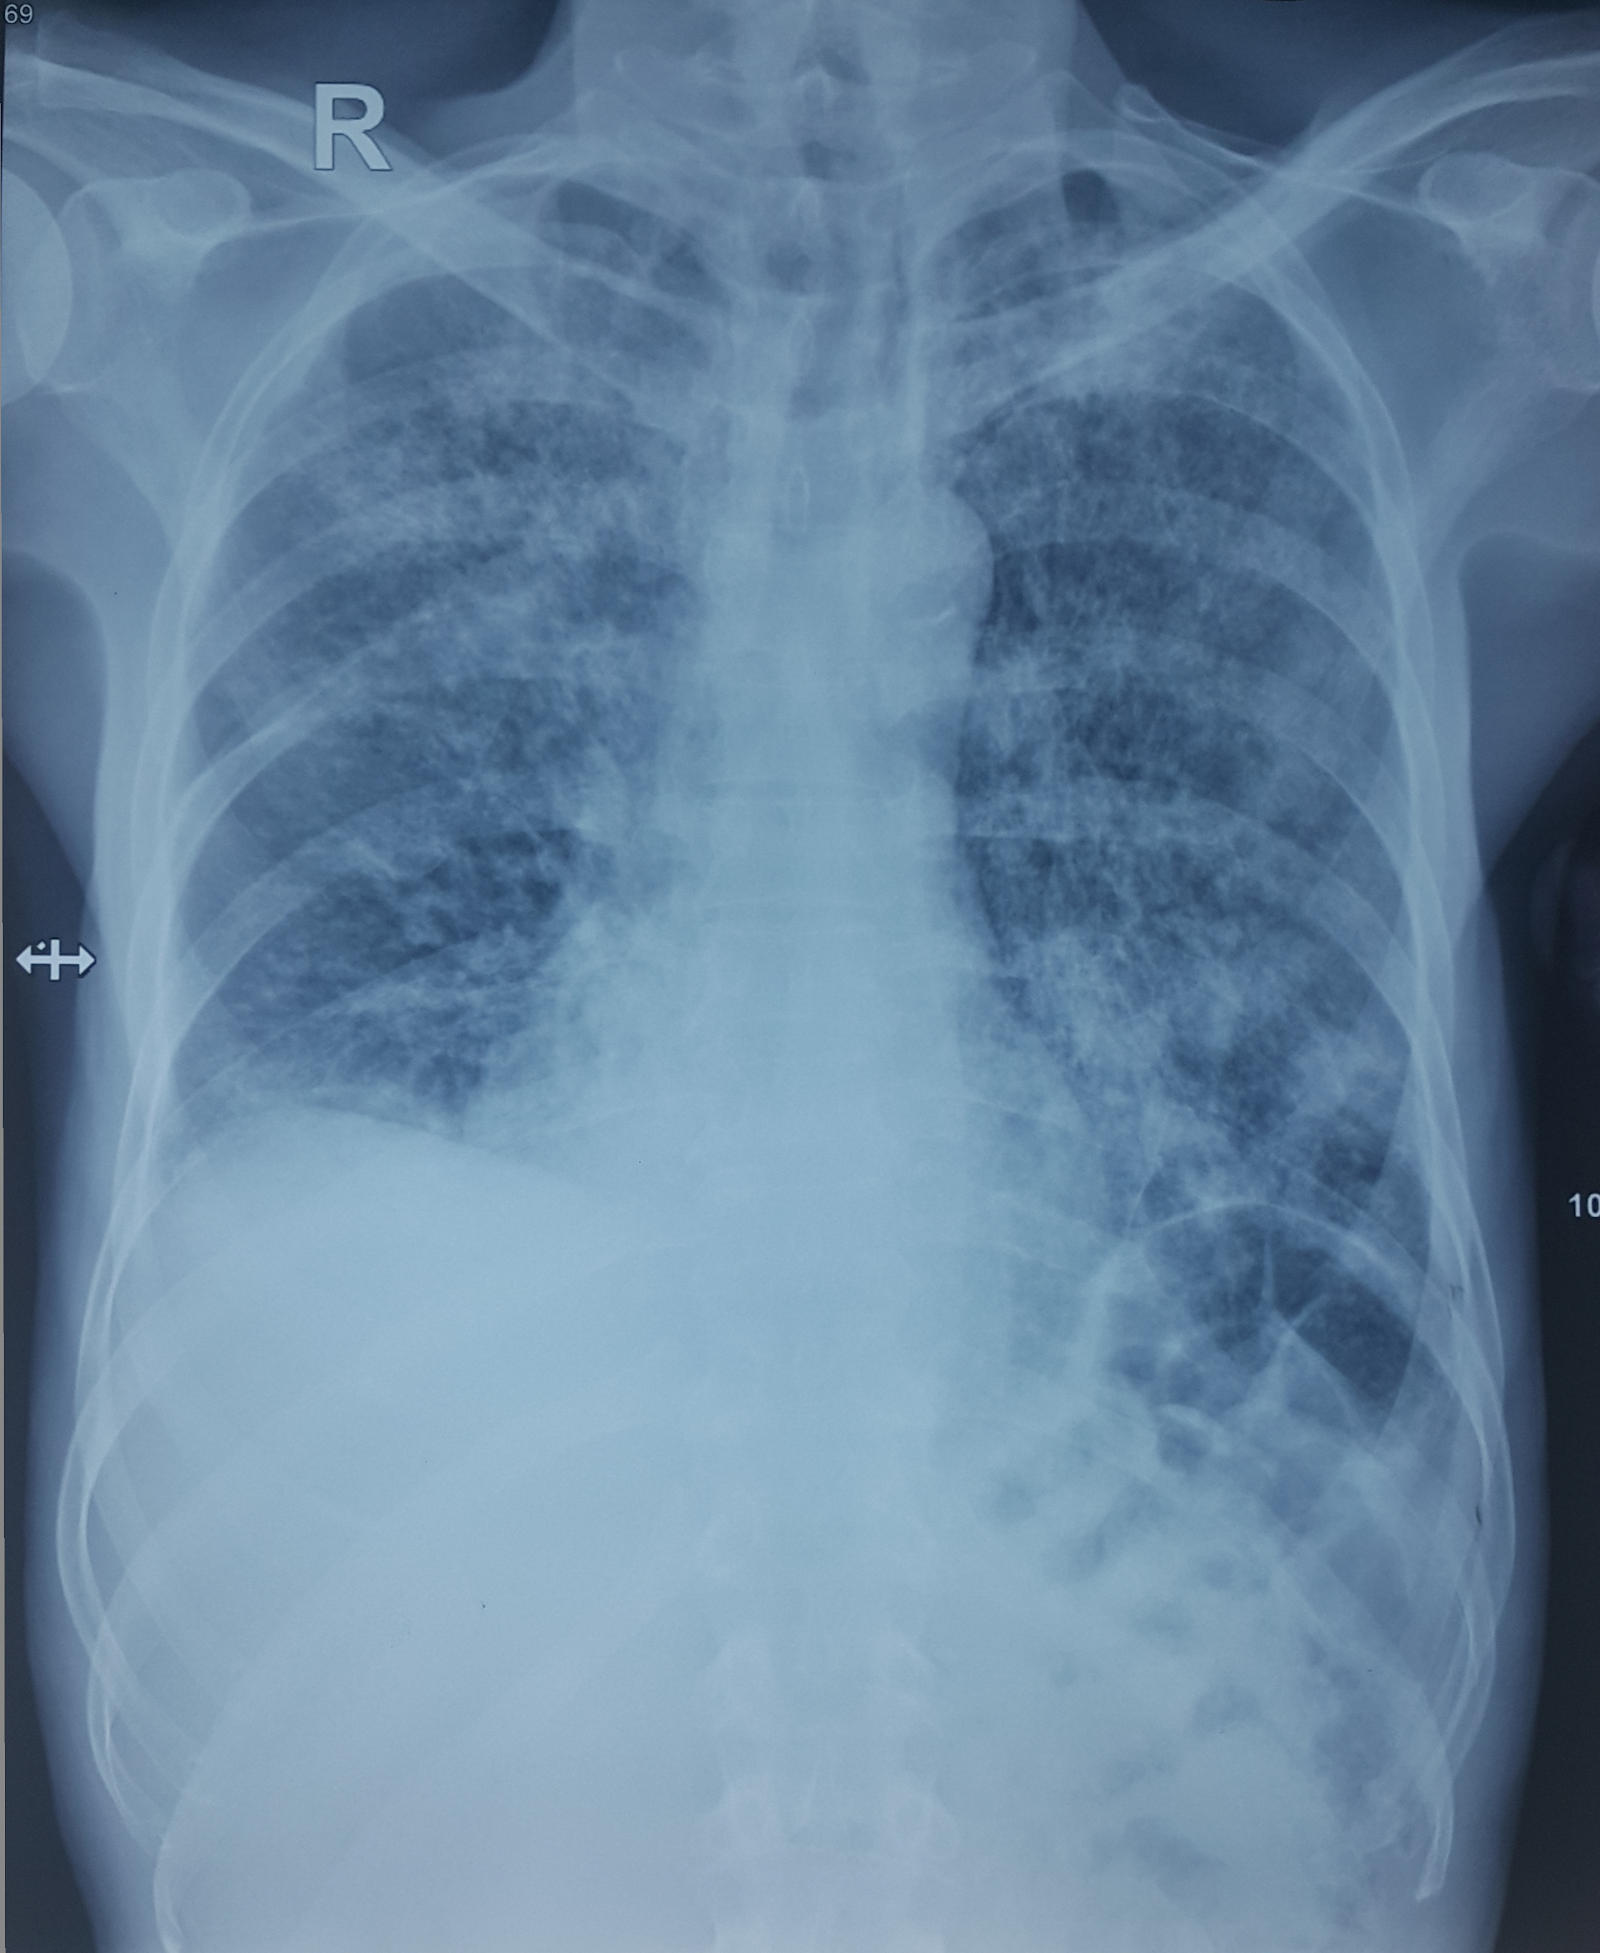

Bệnh nhân nam 69 tuổi vào viện vì ho khạc đàm 1 tháng nay, kèm sụt cân 5 kg

X quang ngực của bệnh nhân

Phân tích X quang ngực